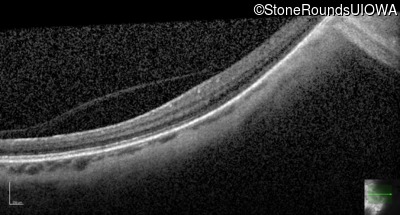

Optical Coherence Tomography - Right - 20/25 -3

Exemplar / OCT Stack

OCT Stack